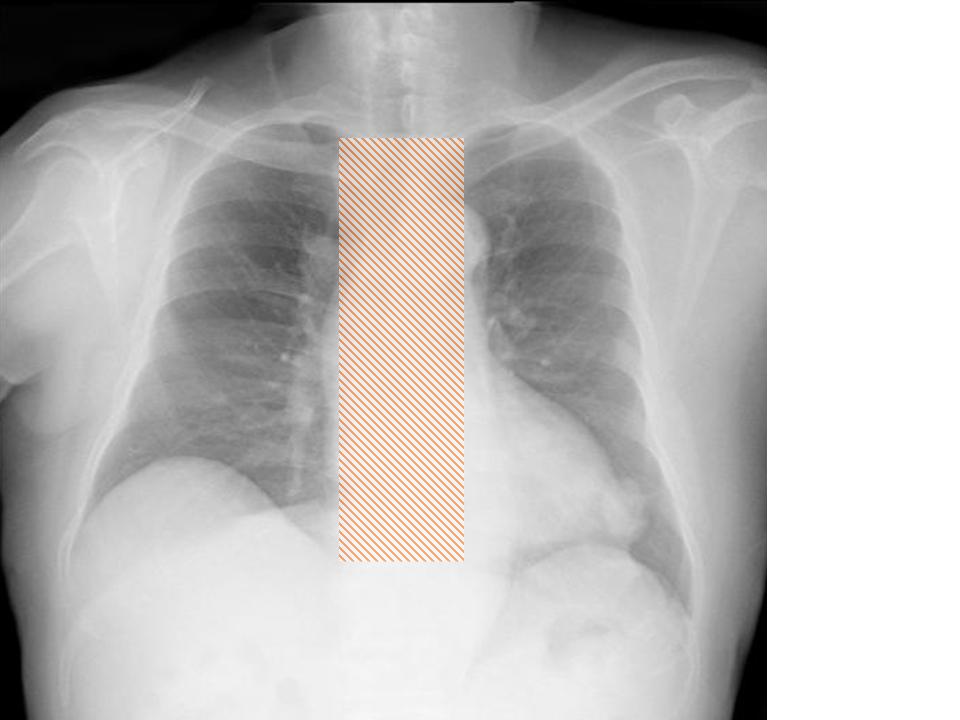

縦隔の所見

縦隔を見るときに、ボーッと見ていては所見を見逃します。

各種の線を追いかけていきましょう。

こちらを見て下さい。

わかりにくいかもしれませんが、このあたり。

気管が追いにくい、無くなっているようにも見えます。